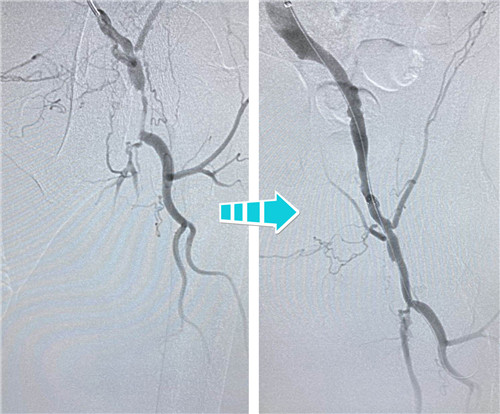

右側(cè)完全閉塞的髂血管順行開通無果,但這也難不倒我們經(jīng)驗(yàn)豐富的鼓醫(yī)和石醫(yī)介入專家們,當(dāng)即決定由“順穿”改行“逆穿”。逆穿導(dǎo)絲難度大,技術(shù)要求高,十分考驗(yàn)術(shù)者的操作手法和預(yù)判,專家團(tuán)隊(duì)經(jīng)過內(nèi)膜下破膜逆行,一次性準(zhǔn)確對(duì)吻成功,同樣擴(kuò)張球囊、植入支架,血流瞬間恢復(fù)暢通。